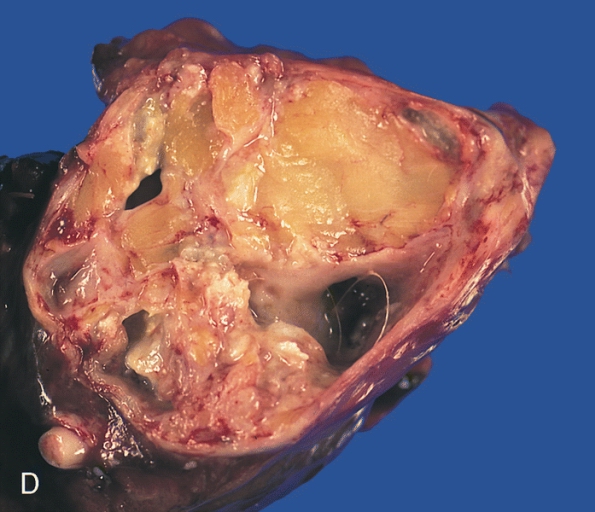

A teratoma is a cystic tumor made of tissue from two or three embryological layers, including the stomach, thyroid, skin, hair, bone, and cartilage.

Teratoma